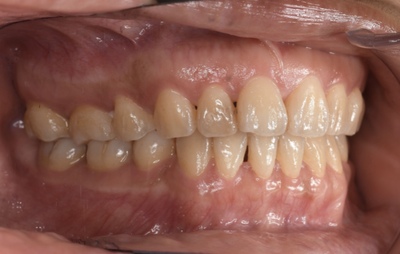

CASE 3

Before

After

基本情報

| 年齢・性別 | 30代・女性 |

| 主訴 | 定期検診 |

| 治療内容 | PMTC |

| 治療期間 | 60分 |

| 治療費 | 5,750円 |

| リスク・副作用 | しみる可能性があります。 |

| 治療方針 | PMTCでステインの除去。 |

| 担当者所見 | ステインが付きやすいため、3カ月毎の定期検診で除去する。 |